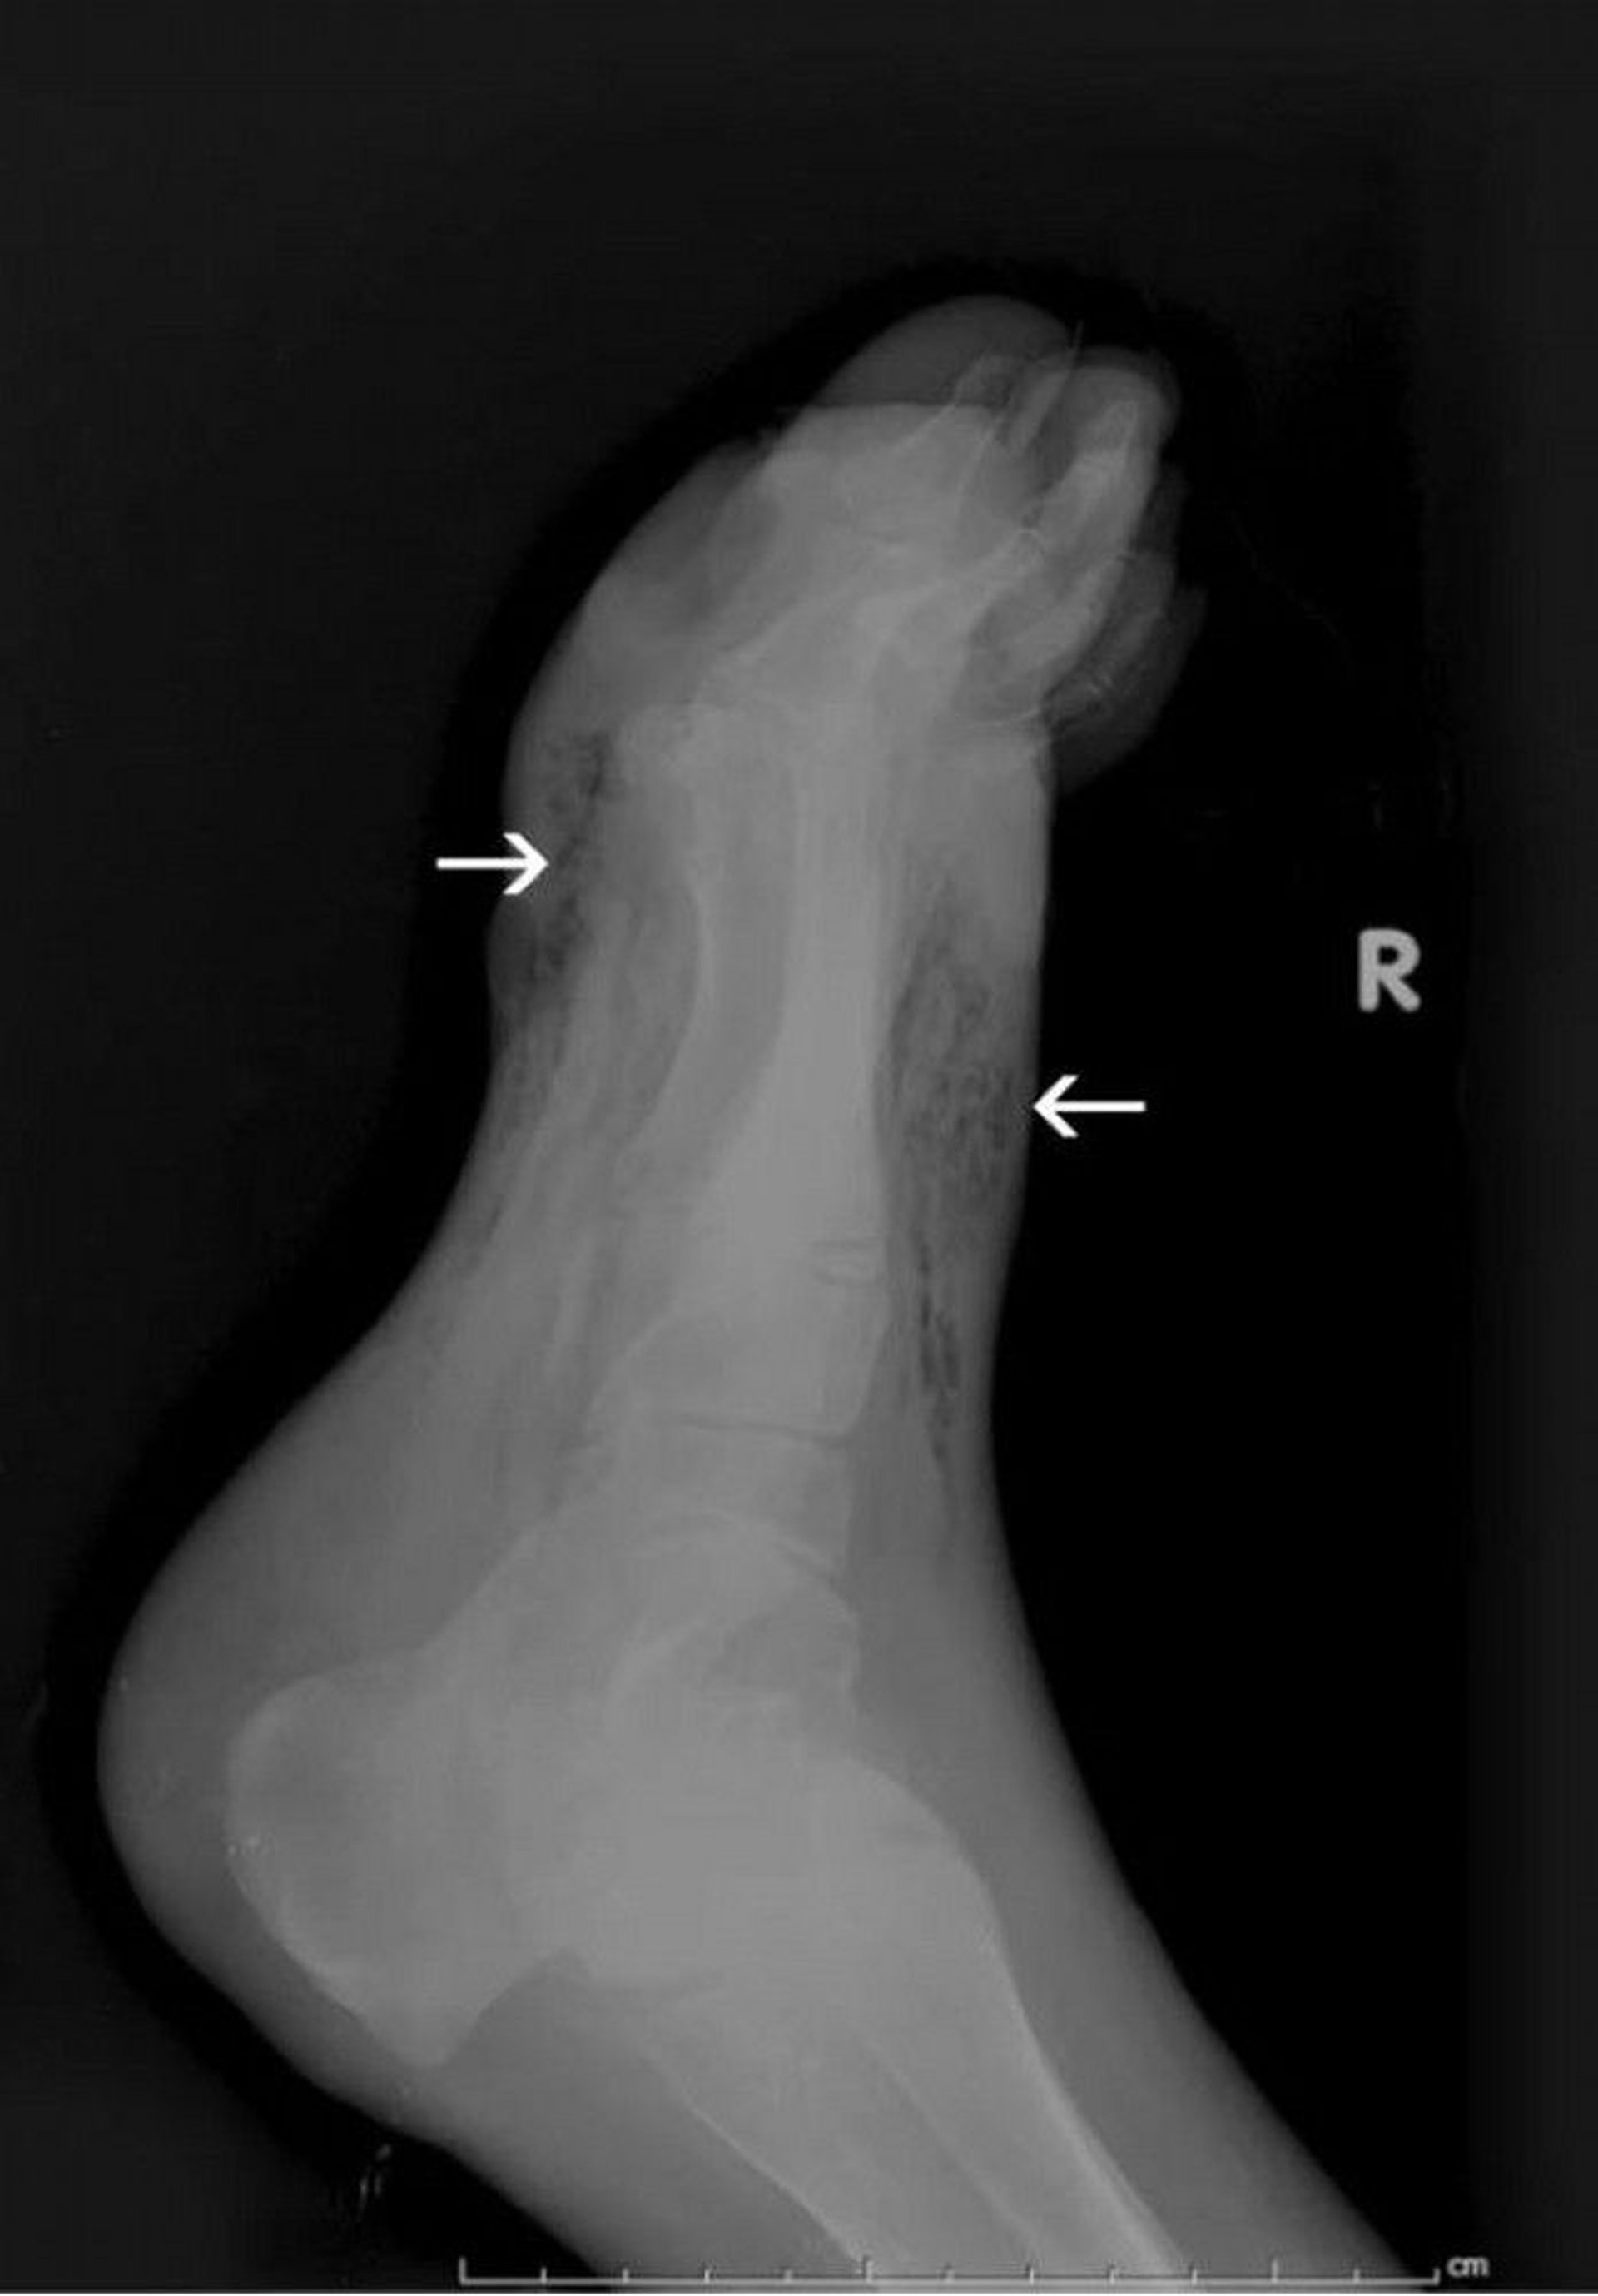

Myonecrosis (Gangrene) of the Foot (Radiograph)

This radiograph shows gas in the soft tissue of the foot (arrows).